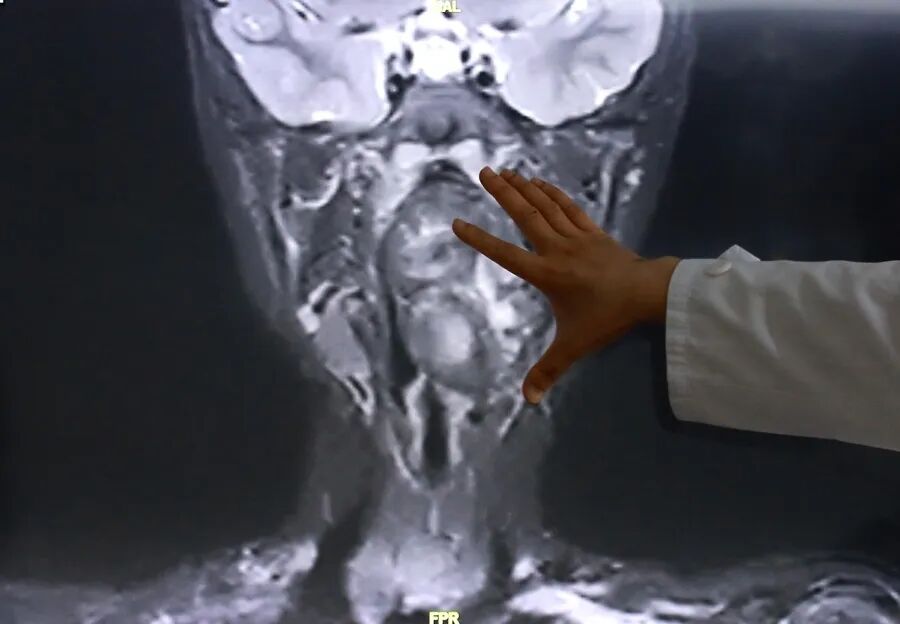

接诊后,综合前期检查及患儿家长自述病情,复旦儿科专家团队高度重视气道梗阻风险,立即启动复杂气道疾病绿色通道,完善增强CT及磁共振检查,明确小亮所患的肿瘤约7×3.5×3厘米,犹如“拳头”般大小。

专家表示,该肿瘤紧邻颈内动静脉并将血管明显向外推移,肿瘤向咽喉腔内隆起,占据大部分口咽及下咽腔,严重压迫声门,随时可能发生窒息。

陈超还表示,“6岁男孩的口咽腔大概在8公分左右,这个孩子的肿瘤已经高达6公分多,整个气道已经完全被这个膨大的肿瘤占据了,只有一条黑颜色的线,这是它透气的空间,再让它继续膨胀下来,它首先出现的一个症状应该是呼吸道的梗阻窒息,会出现窒息致死的可能。”<section style='-webkit-tap-highlight-color: rgba(0, 0, 0, 0);margin: 0px;padding: 0px;outline: 0px;max-width: 100%;box-sizing: border-box !important;overflow-wrap: break-word !important;color: rgba(0, 0, 0, 0.9);font-family: "PingFang SC", system-ui, -apple-system, BlinkMacSystemFont, "Helvetica Neue", "Hiragino Sans GB", "Microsoft YaHei UI", "Microsoft YaHei", Arial, sans-serif;font-size: 17px